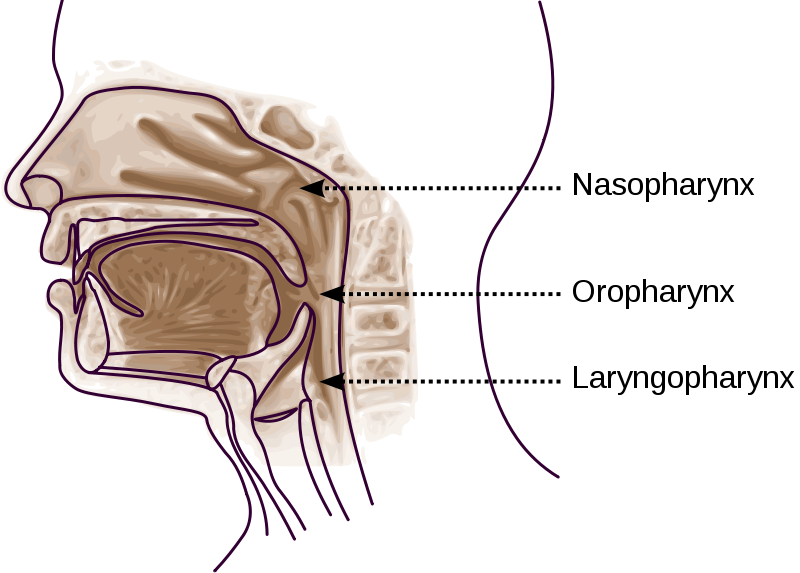

2. Faring

Faring terletak di belakang rongga hidung dan mulut. Faring tersusun dari otot lurik dengan panjang kurang lebih 4 cm. Faring merupakan persimpangan antara saluran pencernaan dengan saluran pernapasan.